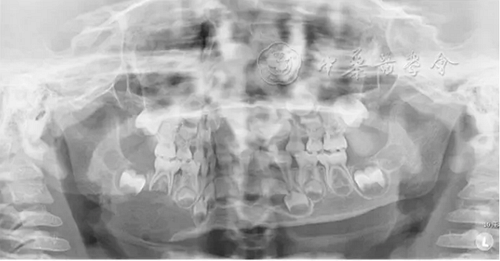

(1)疾病定義及口腔表現(xiàn):中性粒細(xì)胞減少是由于外周血中粒細(xì)胞的絕對值減少而出現(xiàn)的一組綜合征。出生后2周至1歲的嬰幼兒中性粒細(xì)胞低于1×109/L、1歲以上兒童中性粒細(xì)胞低于1.5×109/L時(shí),即可診斷為中性粒細(xì)胞減少癥。當(dāng)中性粒細(xì)胞低于0.5×109/L時(shí)則可診斷為粒細(xì)胞缺乏(agranulocytosis)。根據(jù)中性粒細(xì)胞減少的程度和持續(xù)時(shí)間,病情的輕重不同。病程初期為發(fā)熱,之后表現(xiàn)為反復(fù)感染且難以控制,好發(fā)于呼吸道、泌尿系、皮膚和黏膜等。在口腔主要表現(xiàn)為反復(fù)發(fā)作的口腔炎、口腔潰瘍,牙齒松動(dòng)、乳牙早失,牙齦紅腫、糜爛、齦袋溢膿及牙槽骨喪失等(圖1)。

圖1 4歲中性粒細(xì)胞減少患兒乳牙牙齦明顯紅腫、糜爛

(2)治療原則:主要是去除病因、控制感染、促進(jìn)粒細(xì)胞生成??谇恢委煈?yīng)注意清潔,對糜爛、潰瘍者采取局部對癥治療,牙周潔治以去除菌斑、牙石,進(jìn)行口腔衛(wèi)生宣教維持口腔衛(wèi)生。